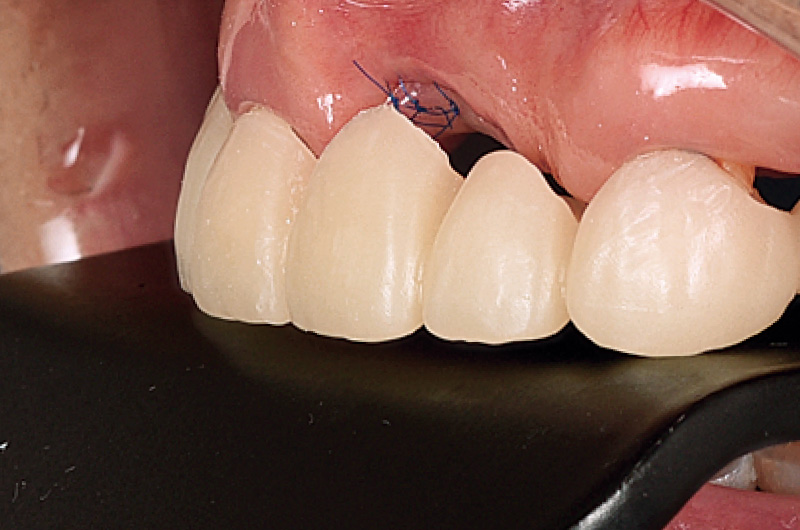

頰舌側のフラップにテンションがかかることなく4mm程度重なることを確認し、縫合へと移った。欠損側歯槽頂にePTFE製の非吸収性モノフィラメント縫合糸にて水平マットレスを2本行い、7-0の縫合糸にて単純縫合を行った。一次創傷治癒を達成するために、raw to rawで縫合できるように努めた。造成量が大きいため、術後大きな腫脹や疼痛はあったものの裂開等もなく、2週間後に抜糸を行った。